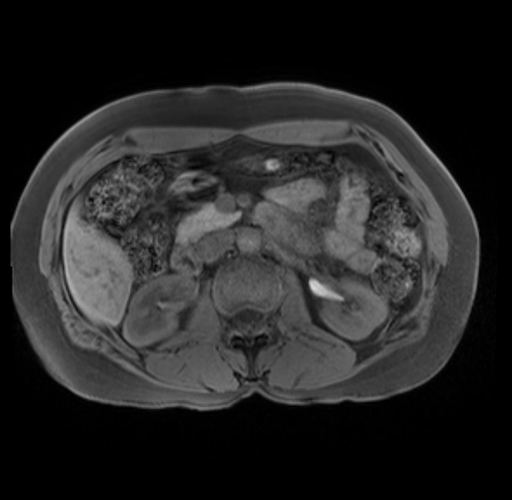

Imaging Analysis

Look through the patient's CT scan to identify any areas of concern for the necessary procedure.

Based on your CT findings, which issue(s) are present and would give reason for "planned slowing down moment(s)" in this case?

Considering a standard distal pancreatectomy procedure, what step(s) of the operation would you do differently in this case?